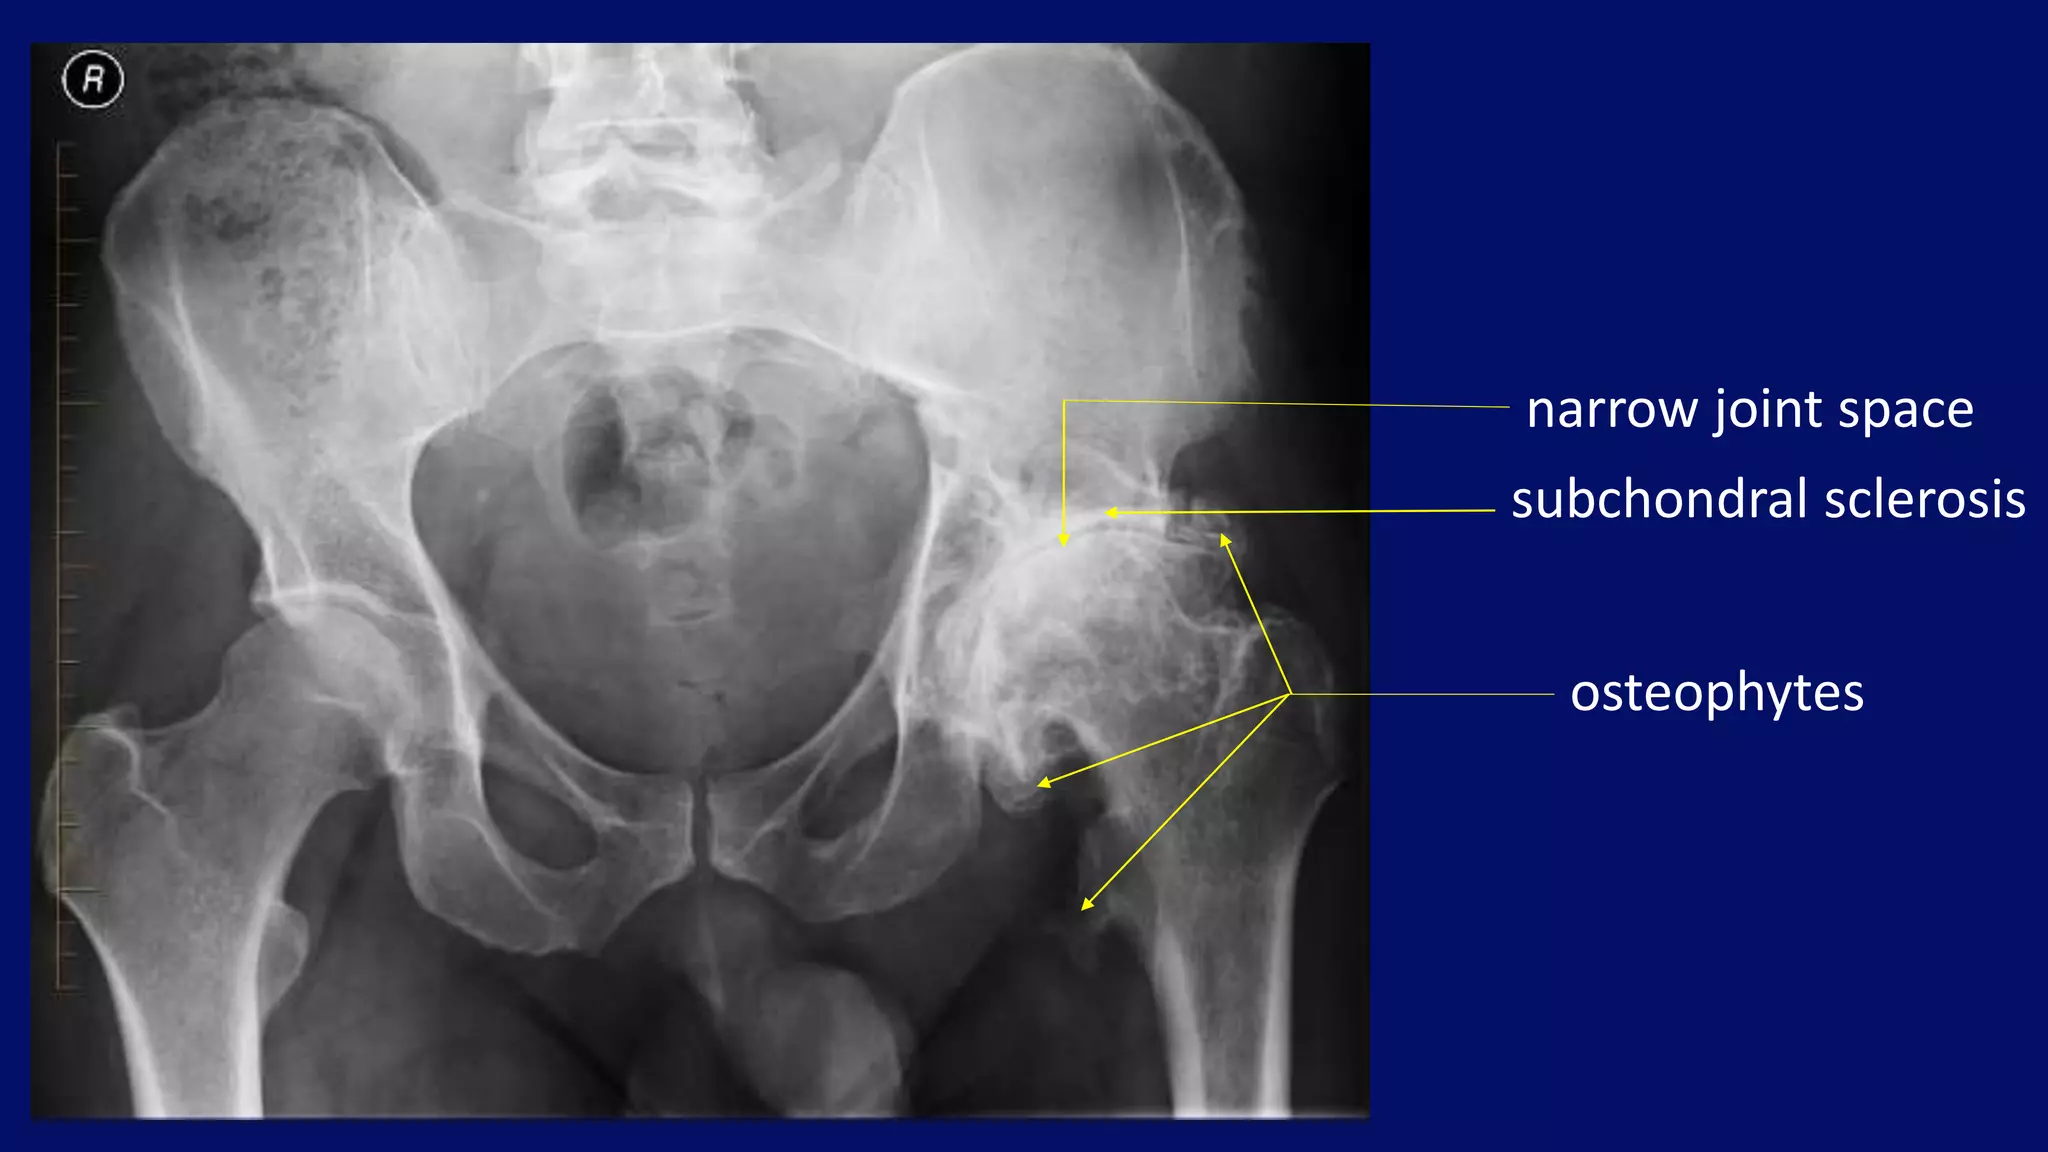

Osteoarthritis of Large joints

narrow joint space

subchondral sclerosis

osteophytes

Right hip osteoarthritis

Superolateral migration of femoral head with typical Eggers cyst in acetabulum.